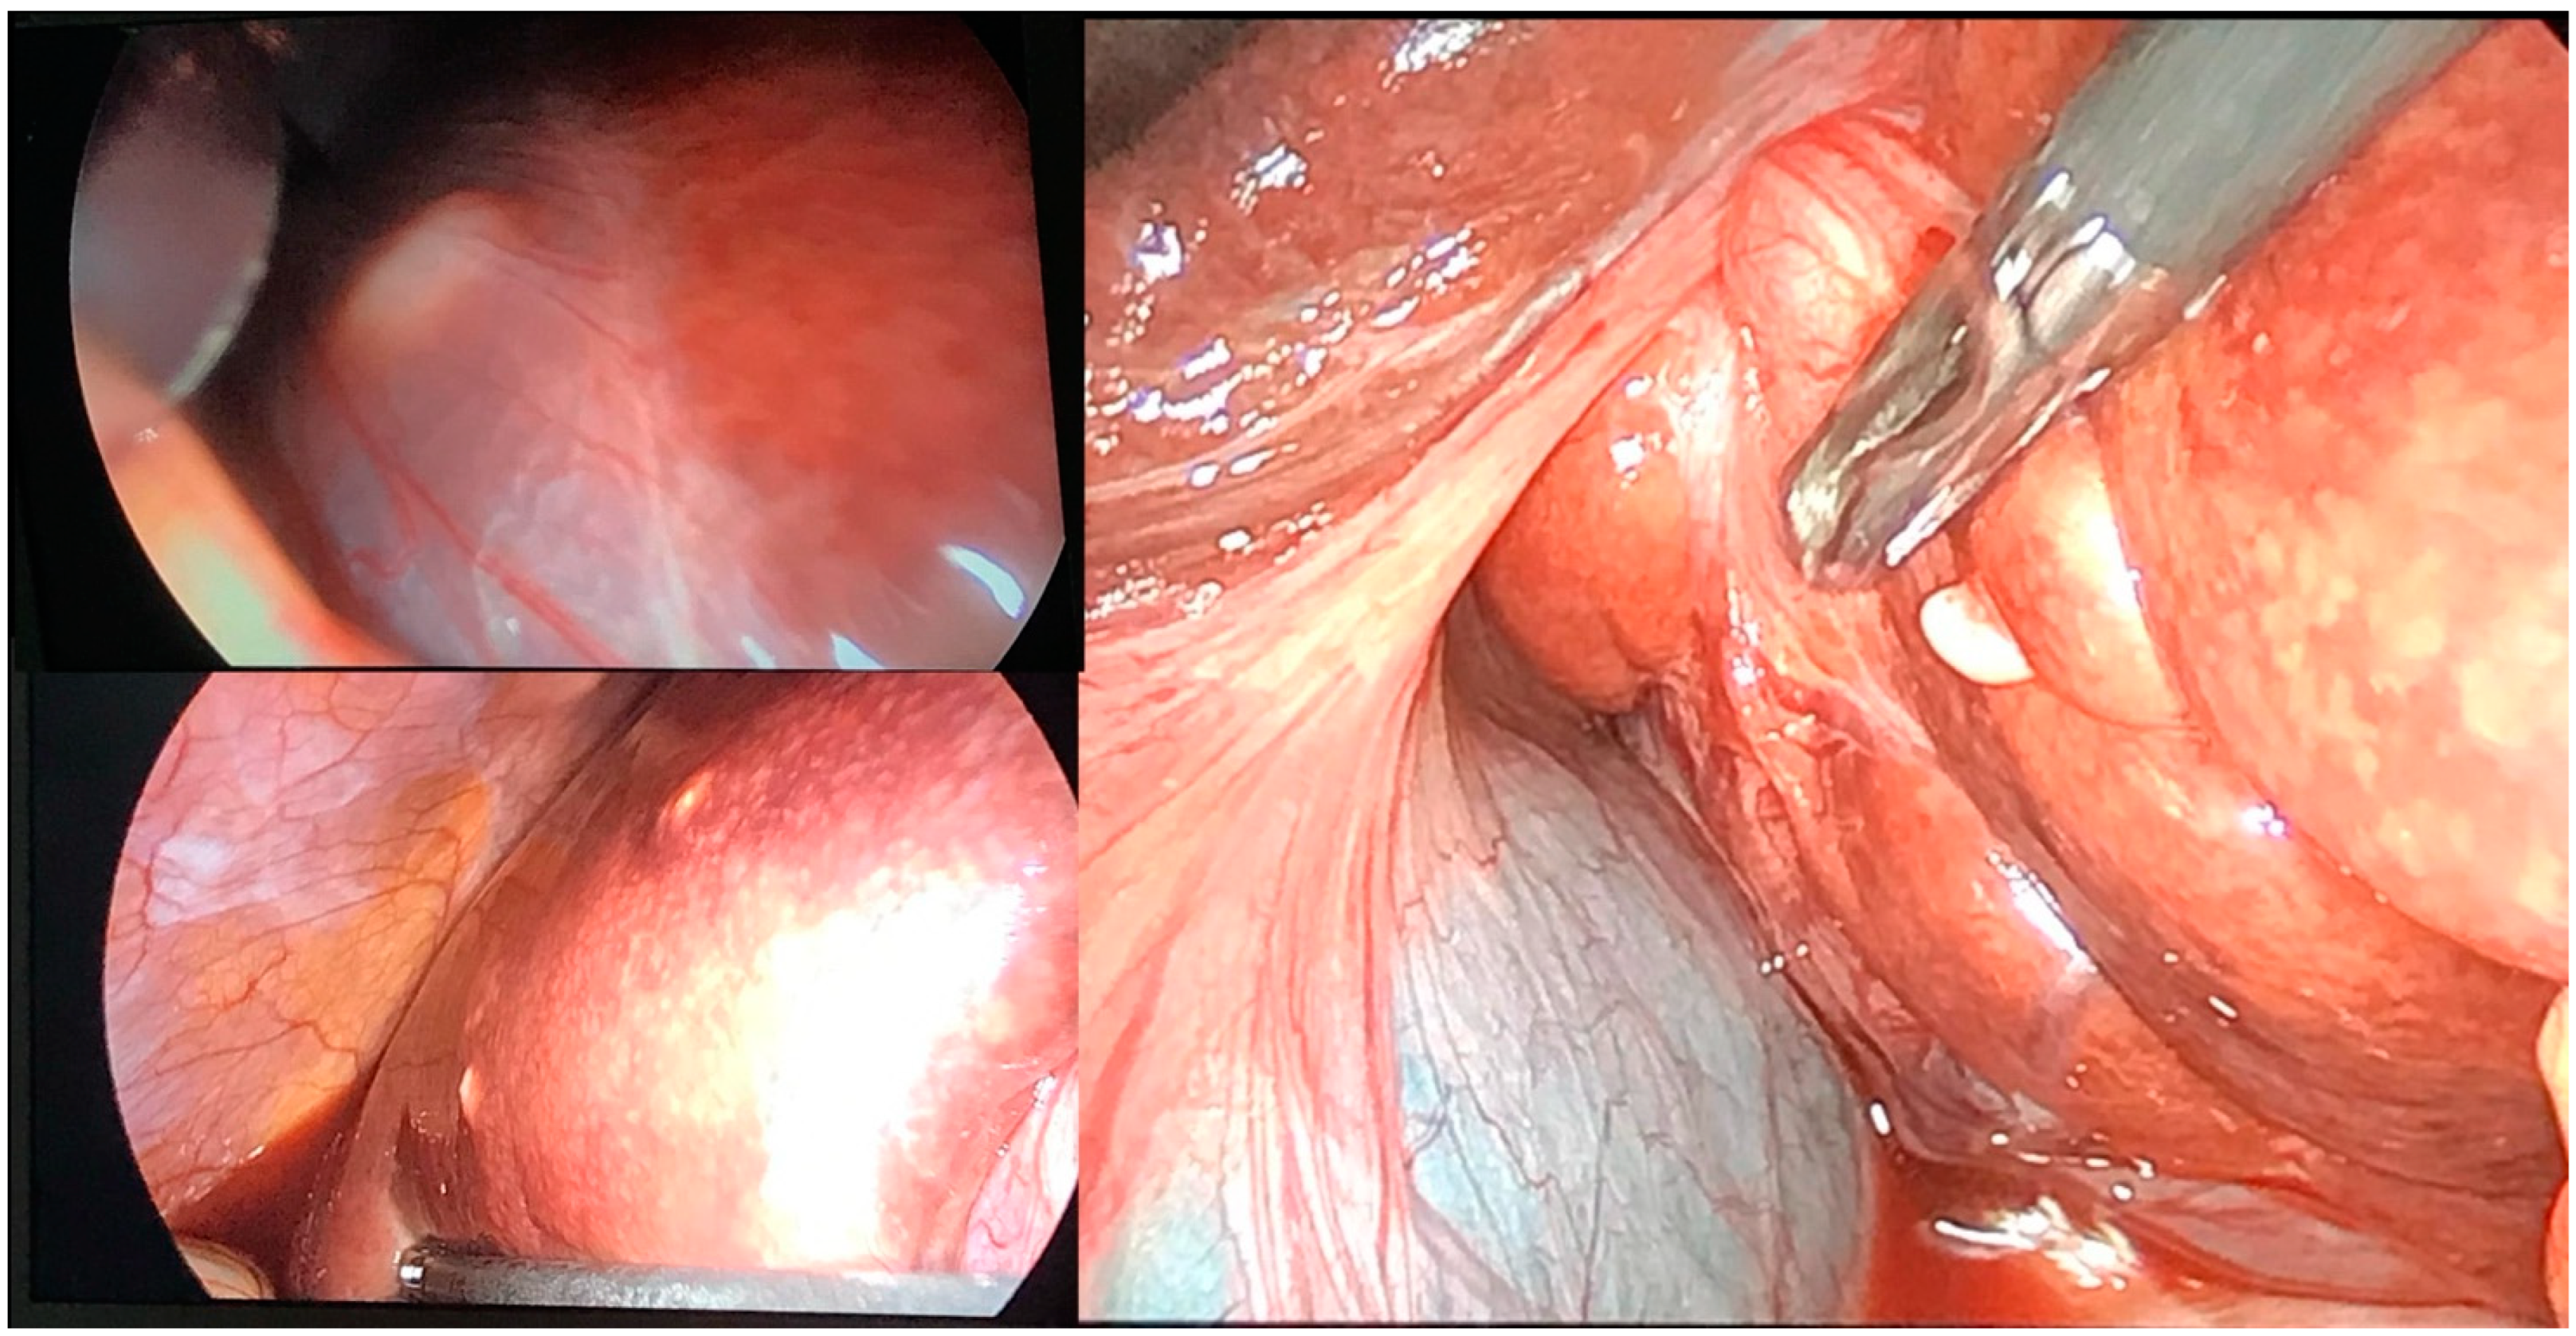

| Diagnostic Methods | MRI, MRCP, ERCP, histopathological examination | CT, MRI, laparoscopic liver biopsy, histopathological examination |

| Tumor Characteristics | Large cystic mass, thin walls, internal septa, papillary projections, enhancing solid components | Large lesion in left hepatic lobe, hyperintensity in T2-weighted images, restricted diffusion, contrast enhancement |

| Treatment | Cyst resection, cholecystectomy | Thrombectomy, chemotherapy, supportive care |

| Surgical Findings | Partially exophytic floating soft mass | Extensive intrahepatic metastases, vascular involvement |